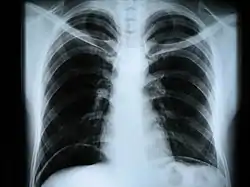

Рентгеногра́фия (от Рентген (фамилия учёного, открывшего этот вид электромагнитных волн)) + греч. gráphō, пишу) — исследование внутренней структуры объектов, которые проецируются при помощи рентгеновских лучей на специальную плёнку или бумагу. Наиболее часто термин относится к медицинскому неинвазивному исследованию, основанному на получении суммарного проекционного изображения анатомических структур организма посредством прохождения через них рентгеновских лучей и регистрации степени ослабления рентгеновского излучения.

Сейчас рентген грудной клетки часто используется для диагностики заболеваний, вызванных инфекциями лёгких. Однако этот метод оказался малоэффективен для обнаружения ранних стадий вирусных пневмоний, вызванных COVID-19.

Американские исследователи во главе с профессором Университета штата Огайо изучили рентгеновские снимки 630 пациентов с подтверждённым коронавирусом и выраженными симптомами. В 89 процентах случаев на рентгене не было заметно никаких отклонений, или они были незначительными. Практика врачей ГКБ №40 в посёлке Коммунарка, которые первыми приняли на себя удар пандемии в России, также подтвердила эти выводы. Тем не менее, на более поздних этапах с помощью рентгенографии можно получить точные и качественные результаты. Именно поэтому в текущей ситуации особенно актуальны портативные аппараты, которые можно применять в палатах пациентов в тяжёлом состоянии[3].

В настоящее время рентгенография остаётся основным методом диагностики поражений костно-суставной системы. Важную роль играет при обследовании лёгких, особенно в качестве скринингового метода. Методы контрастной рентгенографии позволяют оценить состояние внутреннего рельефа полых органов, распространённость свищевых ходов и др.

- рентгенография грудной клетки — инфекционные, опухолевые и другие заболевания,